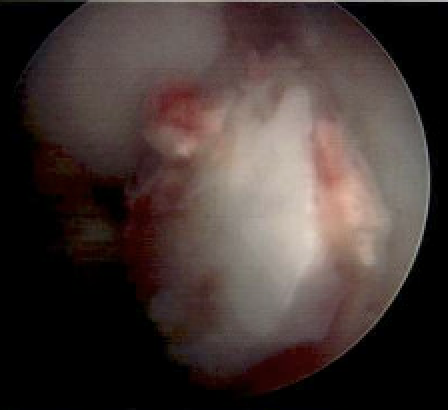

Arthroscopy and fragment removal

Small irreparable chondral fracture from central patella

Osteochondral fragment in notch from uncontained defect lateral femoral condyle